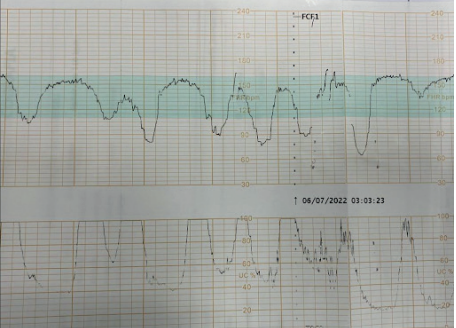

- Desacelerações: Quedas transitórias da FCF, classificadas em:

- Tipo I (Precoce ou DIP I): Queda gradual e simétrica da FCF, cujo ponto mais baixo (nadir) coincide com o pico da contração uterina. É causada pela compressão do polo cefálico (reflexo vagal) e não se associa à hipóxia.

- Tipo II (Tardia ou DIP II): Queda gradual com nadir posterior ao pico da contração. Este padrão indica insuficiência uteroplacentária e hipóxia fetal.

- Tipo III (Variável ou Umbilical): Queda abrupta e de morfologia variável, causada pela compressão do cordão umbilical. Podem não estar associadas a sofrimento fetal, mas critérios como duração superior a 60 segundos, queda abaixo de 70 bpm e retorno lento à linha de base indicam mau prognóstico.

- Padrão Sinusoidal: Um padrão ondulatório, rítmico e regular, que é um sinal ominoso de anemia fetal grave e hipoxemia, com alto risco de óbito intraútero.

Os traçados da CTG intraparto são classificados em três categorias:

- Categoria 3: Traçado anormal. Inclui padrão sinusoidal ou ausência de variabilidade associada a desacelerações tardias/variáveis recorrentes ou bradicardia. A conduta é a realização imediata de medidas de ressuscitação intrauterina e parto pela via mais rápida.